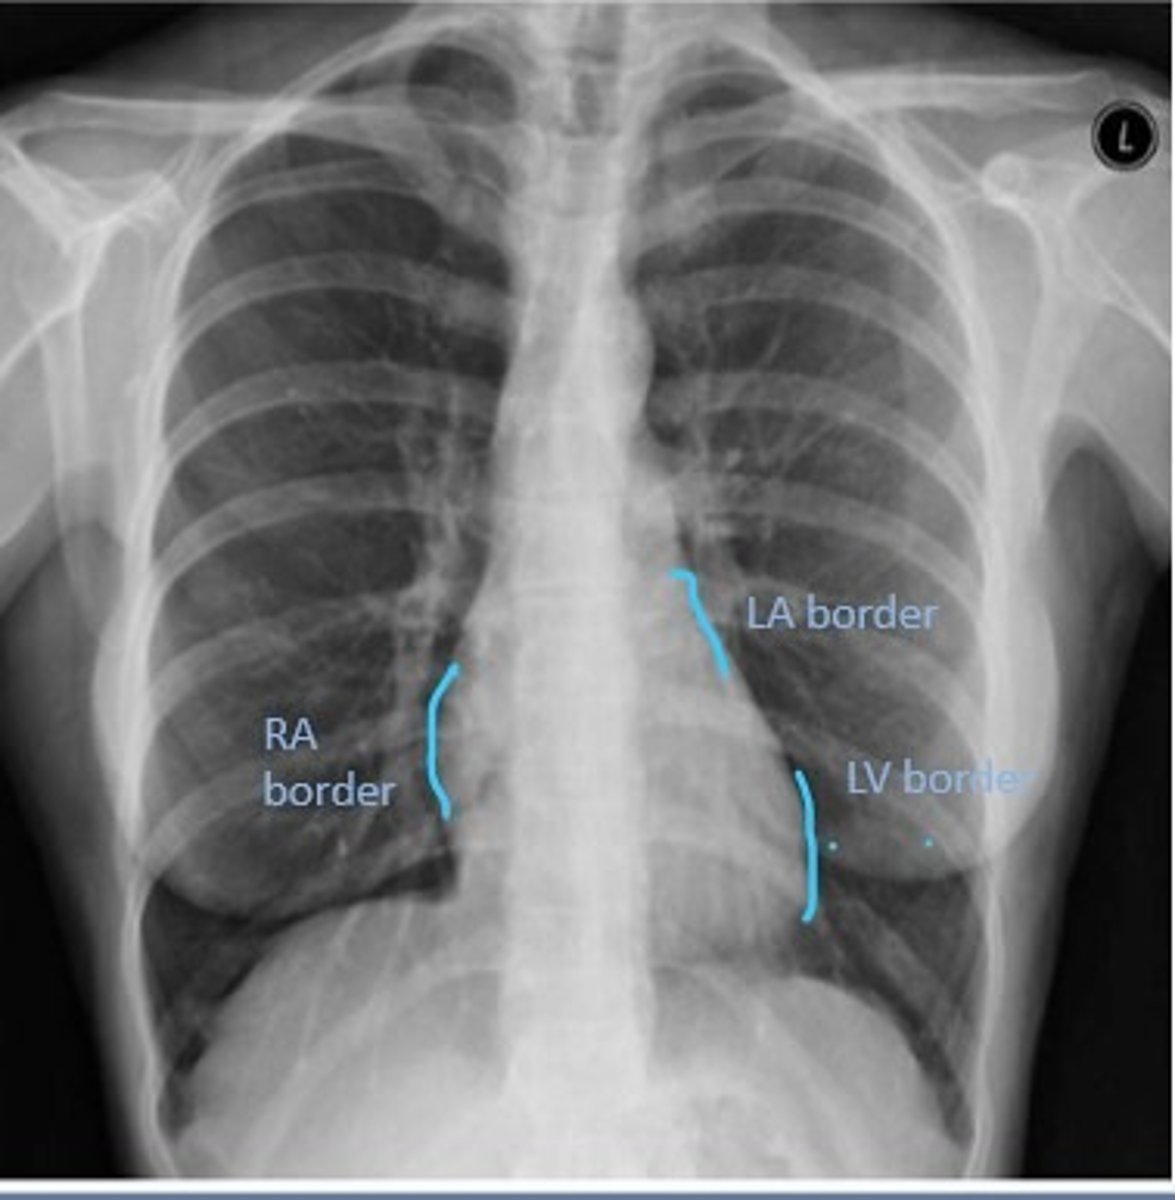

Right Cardiac Border

An area formed by the right atrium

Left Cardiac Border

An area formed by the left ventricle